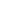

Intrapulmonary Bronchogenic Cyst in an Infant: Rare Presentation and Insights From Literature

Ramyasree Bade

, Shailesh Solanki

, Shivani Dogra

, et al.

Adv Pediatr Surg 2025;31(2):87-92.